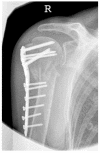

The aim of this study was to create a novel complication classification for osteosynthesis-related complications following angular stable plating of the proximal humerus subsuming the influence of these complications on clinical outcome in relation to fracture morphology and consequent revision strategies. A total of 1047 proximal humerus fractures with overall 193 osteosynthesis-associated complications (24.5%) were included. The following complication types could be clarified: complication Type 1 is defined by mild varus (<20°) or valgus displacement of the humeral head without resulting in a screw cutout through the humeral head cortex. Type 2a is defined by varus displacement (<20°) of the humeral head associated with screw cutout through the humeral head cortex. Type 2b complication is limited to displacement of the greater tuberosity, lesser tuberosity, or both tuberosities. Complication Type 2c is defined by severe varus dislocation (>20°) of the humeral head with screw cutout at the humeral head cortex. Complication Type 3 describes a displacement of the angular stable plate in the humeral shaft region with associated shaft-sided screw cutout, while the position of the humeral head remains static. Complication Type 4 is characterized by the occurrence of AVN with or without glenoidal affection (4a/b). Clinical outcome according to the constant score was mainly affected by type 2-4, leading to a deteriorated result. Depending on the type of complication, specific revision strategies can be considered. Additionally, more complex fracture patterns fostered the incidence of complications.